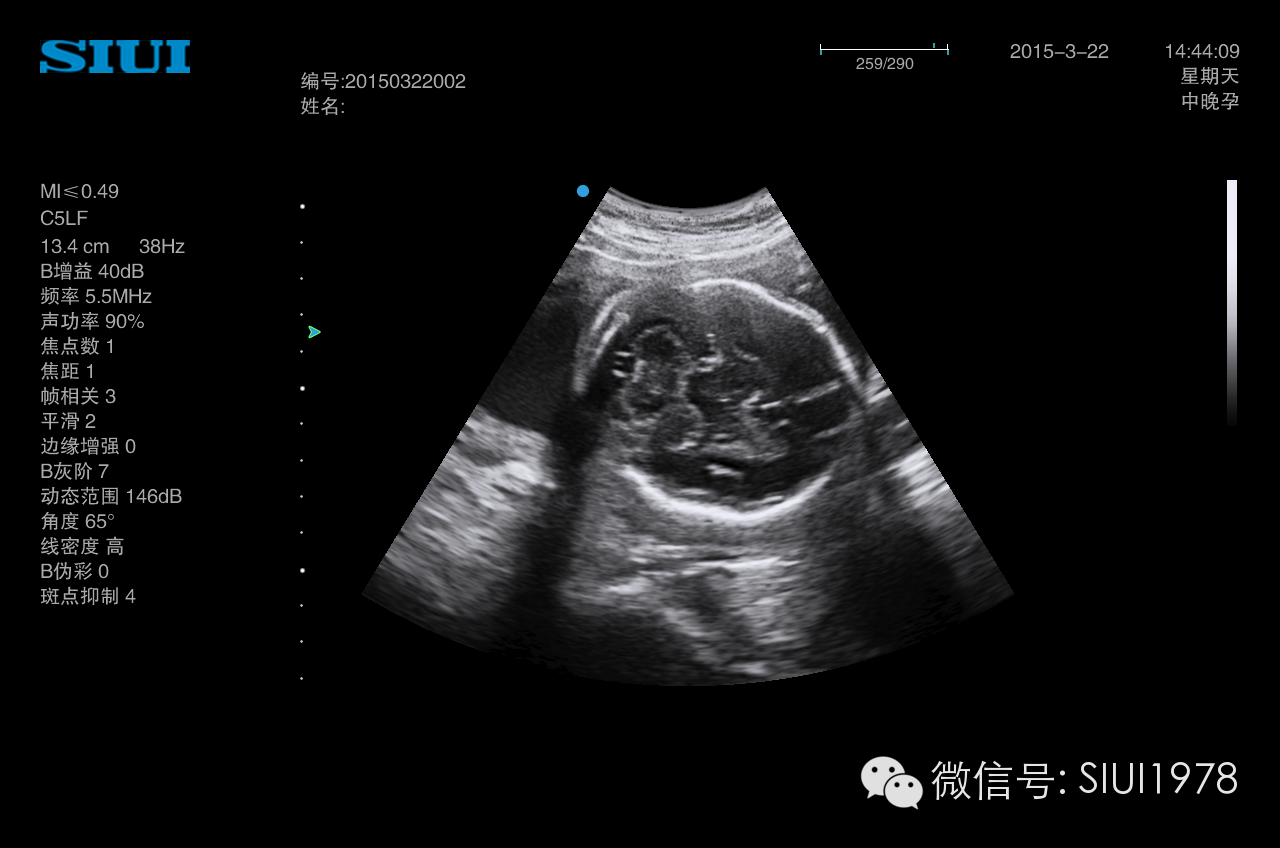

超声胎儿图片

超声胎儿图片,

胎儿唇裂超声图片汇总处

怀孕142周的3d胎儿超声图